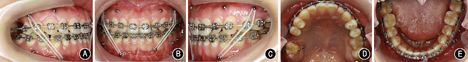

向患者详细阐述手术提前方案与传统术前正畸方案的优缺点及治疗风险后,患者自愿接受手术提前方案并签署知情同意书。术前拔除

残根、

阻生智齿。正畸初始弓丝为0.356 mm(0.014英寸)镍钛圆丝,术前弓丝为0.406 mm(0.016英寸)镍钛圆丝。并于

近中腭侧、

近中颊侧植入助攻型钛合金微螺钉作为骨性支抗,持续轻力(0.49~0.98 N)矫正

的颊向倾斜和

的舌向倾斜。经过2个月术前正畸即解除手术

干扰,转移咬合关系至

架,做模型外科操作,可获得稳定的术后咬合。转正颌外科手术,此患者虽然存在上颌后缩,但鼻唇角尚在能接受范围内,而鼻旁区凹陷更明显。因此提出两个手术方案:①双颌手术;②下颌单颌手术辅助鼻旁区植骨。患者及家属选择方案②行下颌双侧升支矢状劈开术、颏部成形术和鼻旁区植骨术,并于全麻下在上下颌前牙区及后牙区行种植体支抗植入术。术后2周去除颌间牵引,术后4周去除咬合板后行术后正畸。术中及术后于种植体支抗间行颌间牵引预防复发。术前正畸2个月,术后正畸13个月,总疗程16.5个月。

像;B:正面

像;C:左侧

像;D:上颌

面像;E:下颌

面像